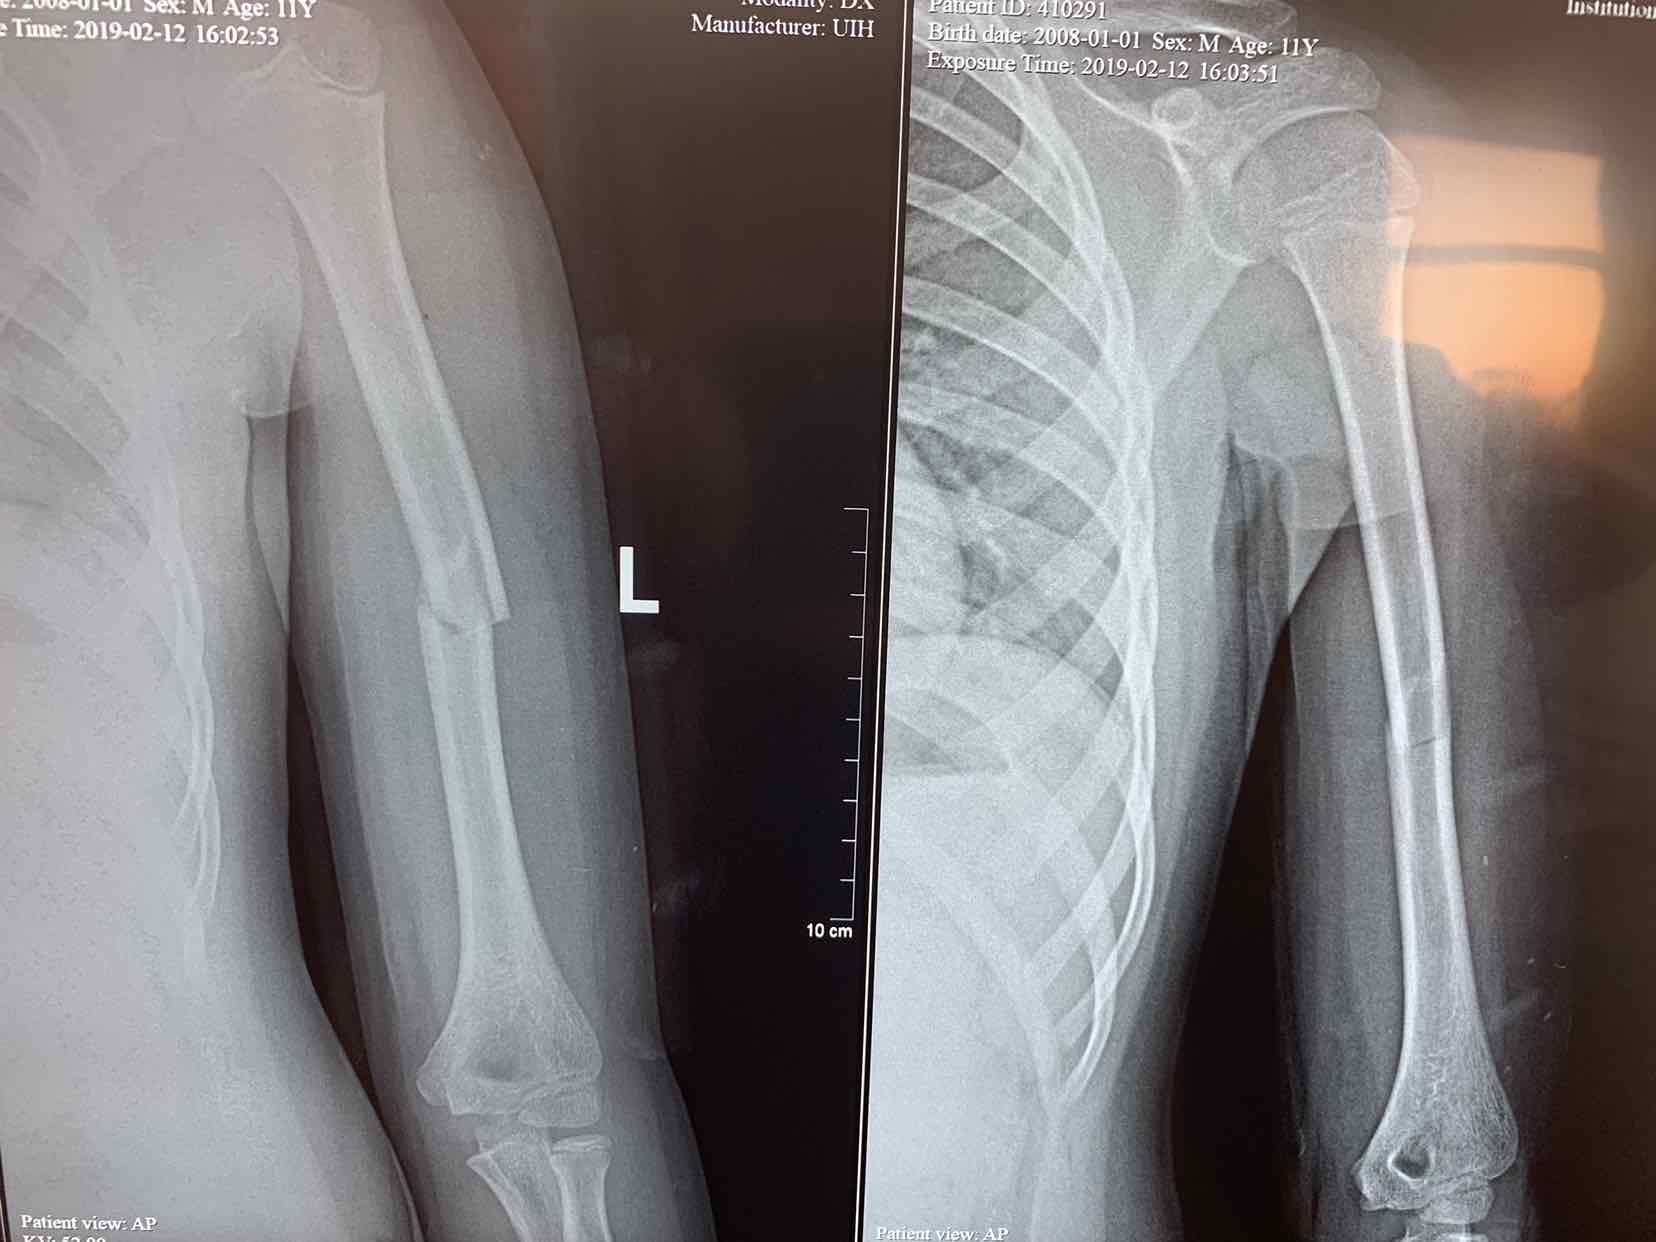

车撞伤,左侧上臂肿痛,畸形,活动受限一小时。患者于一小时前在玩耍时被机动车撞伤,当即左侧上臂肿痛。畸形,不敢活动,立即来诊,门诊拍片提示,左侧肱骨中段骨折,断端移位,对位欠佳。门诊以巡测肱骨骨折收入院治疗。

查体 见患者左侧上臂局部肿胀,压痛,有明显骨折端异常活动,皮肤感觉正常,左手活动自如。拍片提示左侧肱骨中段骨折,断端移位,对位欠佳。。